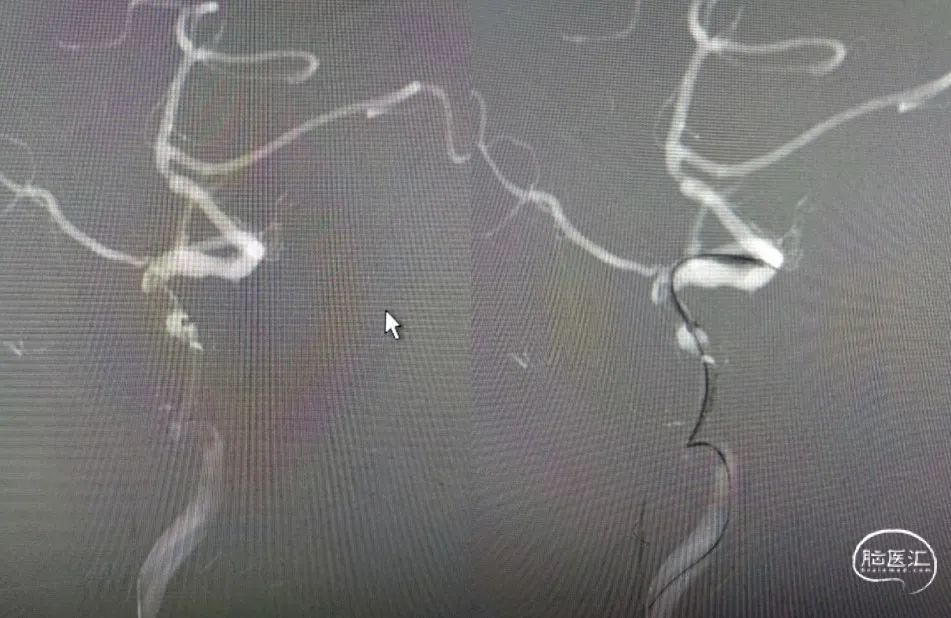

(术后14d CTA)RMCA-M1支架植入术后改变。

NOVA DES®应用——2022年随访:

2022年6月23日:左上肢肌力2+级;左下肢肌力5-级;可流利行走;言语欠流利;神志清楚;NIHSS 5分;mRS 2分。

术后影像及检查

术后正位造影。

术后侧位造影